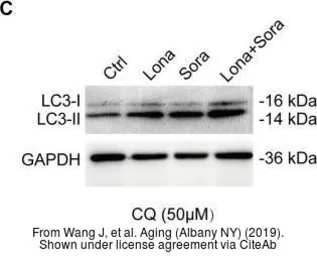

The data was published in the Cancer Med in 2020. PMID: 32324343